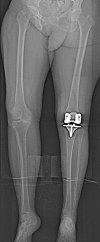

Methods: We retrospectively reviewed 57 patients undergoing primary TKAs using patient-specific custom cutting blocks for osteoarthritis and compared them with 57 matched patients undergoing TKAs with traditional instrumentation during the same period (January 2009 to September 2010). At baseline, the groups were comparable with respect to age, sex, and BMI. We collected data on operative time (total in-room time and tourniquet time) and measured component alignment on plain radiographs.

Results: On average, TKAs performed with patient-specific instrumentation had similar tourniquet times (61.0 versus 56.2 minutes) but patients were in the operating room 12.1 minutes less (137.2 versus 125.1 minutes) than those in the standard instrumentation group. We observed no difference in the femorotibial angle in the coronal plane between the two groups.